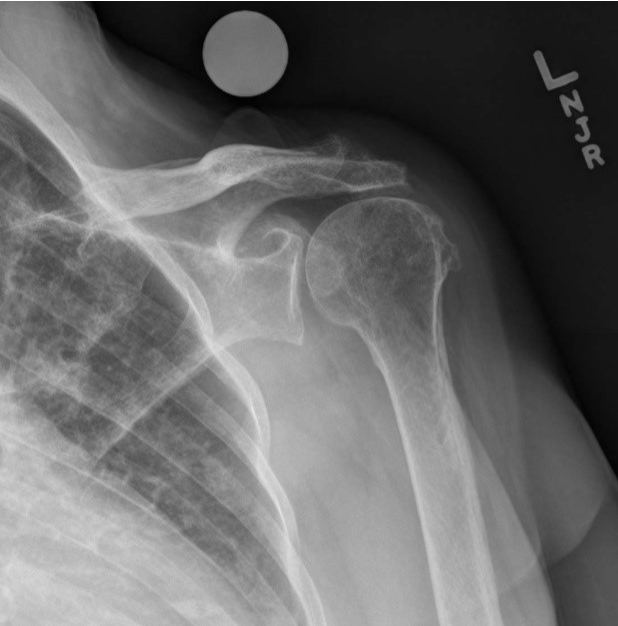

Which of the following statements are correct regarding the radiograph shown?

1 - It demonstrates a scapular Y projection.

2 - The axillary and vertebral borders are superimposed.

3 - It is performed to demonstrate shoulder dislocation.

A - 1 only

B - 2 only

C - 1 and 2 only

D - 2 and 3 only

A

The Correct Answer is: B

The radiograph in the Figure illustrates a lateral projection of the scapula. The axillary and vertebral borders are superimposed. The acromion and coracoid process are visualized; the coracoid process is partially superimposed on the axillary portion of the third rib. A scapular Y projection is often performed to demonstrate shoulder dislocation, but the affected arm is left to rest at the patient’s side; the arm in this radiograph is abducted somewhat to better view the body of the scapula.